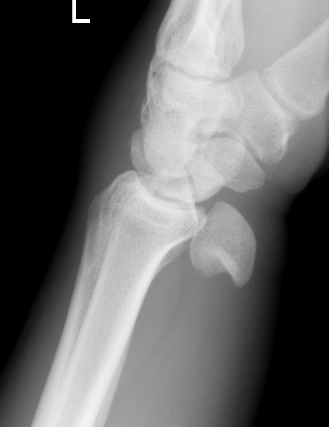

Lateral xray

Distal radius / lunate / capitate: not aligned, spilled teacup

Normal versus spilled tea cup appearance on lateral with spilled tea cup